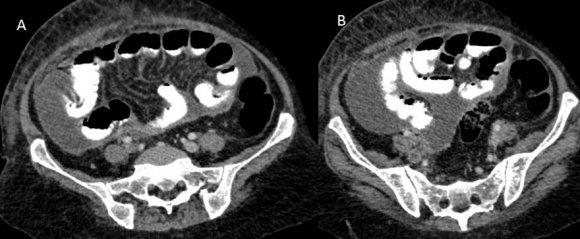

CT scan of the abdomen and pelvis (Figures: 4-8) showed changes of fatty infiltration in the liver. Multiple well-defined lymph nodes of size 1 to 2 cms were noted at portahepatis, peripancreatic region, celiac axis, left renal hilum, preaortic and para-aortic regions, precaval and paracaval regions and in right internal iliac region. Most of the lymph nodes showed peripheral enhancement with central hypodense areas of necrosis. A conglomerated matted lymph nodal mass of size 35 x 24 mm noted in the precaval region. Multiple ill-defined and nodular soft tissues infiltrate noted within the mesentery. Moderate ascites noted with mild peritoneal enhancement without septations. Ileo-caecal junction and other bowel loops appeared normal. IVC distal to renal veins showed persistent filling defect of size 10 (Anteroposterior) x 16 (Transverse) mm extending over a length of 67mm with peripheral enhancement in contrast study extending to right common iliac vein suggestive of IVC and right common iliac vein thrombosis.

Given the above findings, the possibility of tuberculous etiology with IVC thrombosis was considered.